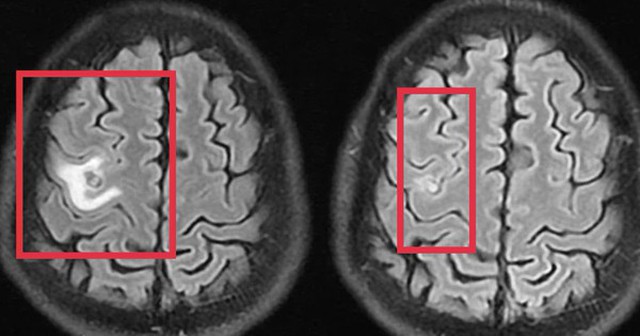

Hình ảnh ổ sán não trước và sau điều trị. Ảnh: BVCC

Chụp cộng hưởng từ sọ não phát hiện một nang nhỏ ở thùy trán trái, kích thước khoảng 11 x 7 mm, kèm phù não nhẹ. Hình ảnh gợi ý tổn thương do ký sinh trùng hơn là u não nguyên phát. Xét nghiệm huyết thanh học kháng thể kháng sán dây chó dương tính, xác định chẩn đoán tổn thương não do ký sinh trùng.

Bệnh nhân được điều trị theo phác đồ, kiểm soát triệu chứng và theo dõi sát diễn biến thần kinh. Sau 10 ngày, tình trạng cải thiện rõ rệt, bệnh nhân hết tê tay, không co giật, đau đầu hay chóng mặt biến mất, toàn trạng ổn định. Bệnh nhân xuất viện và tiếp tục điều trị ngoại trú đủ liệu trình 4 tuần.

Khi tái khám gần một tháng sau, chụp cộng hưởng từ cho thấy nang não thu nhỏ rõ, phù não giảm, không còn dấu hiệu tiến triển, đáp ứng điều trị tốt.